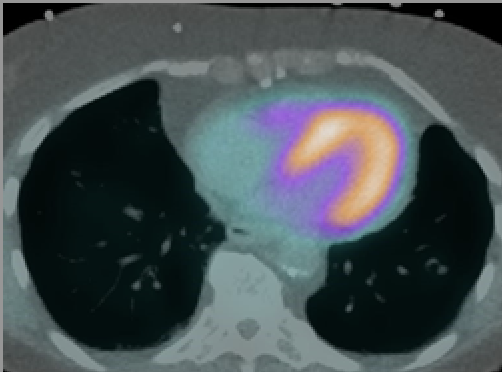

Authored and endorsed by ASNC and the American Association of Physicists in Medicine (AAPM), Society of Cardiovascular Computed Tomography (SCCT) and the Society of Nuclear Medicine and Molecular Imaging (SNMMI), the new guideline highlights how SPECT/CT and PET/CT testing improve diagnostic accuracy and risk-stratification in patients with known or suspected coronary artery disease as well as the clinical value of hybrid nuclear-CT imaging in assessing infection, inflammation, viability and hibernation in cardiac patients.

“Hybrid imaging is helping cardiology teams enhance image quality and obtain new information that impact treatment decisions and our patients’ long-term outcomes,” says ASNC President-elect Mouaz H. Al-Mallah, MD, MSc, FASNC, cardiac PET chair at Houston Methodist DeBakey Heart and Vascular Center and the new guideline’s lead author. “Assessing atherosclerosis burden in hybrid imaging improves the diagnostic accuracy of MPI studies and help clinicians identify high-risk patients and treat them accordingly. The question is not whether today’s cardiac imaging labs should adopt hybrid imaging but rather how to adapt their labs for the routine use of SPECT/CT and PET/CT. There are practical day-to-day issues that can become obstacles for labs. We developed this guideline to show the options available for managing the practical issues, thus making hybrid nuclear-CT imaging more accessible for patients who will benefit from it.”